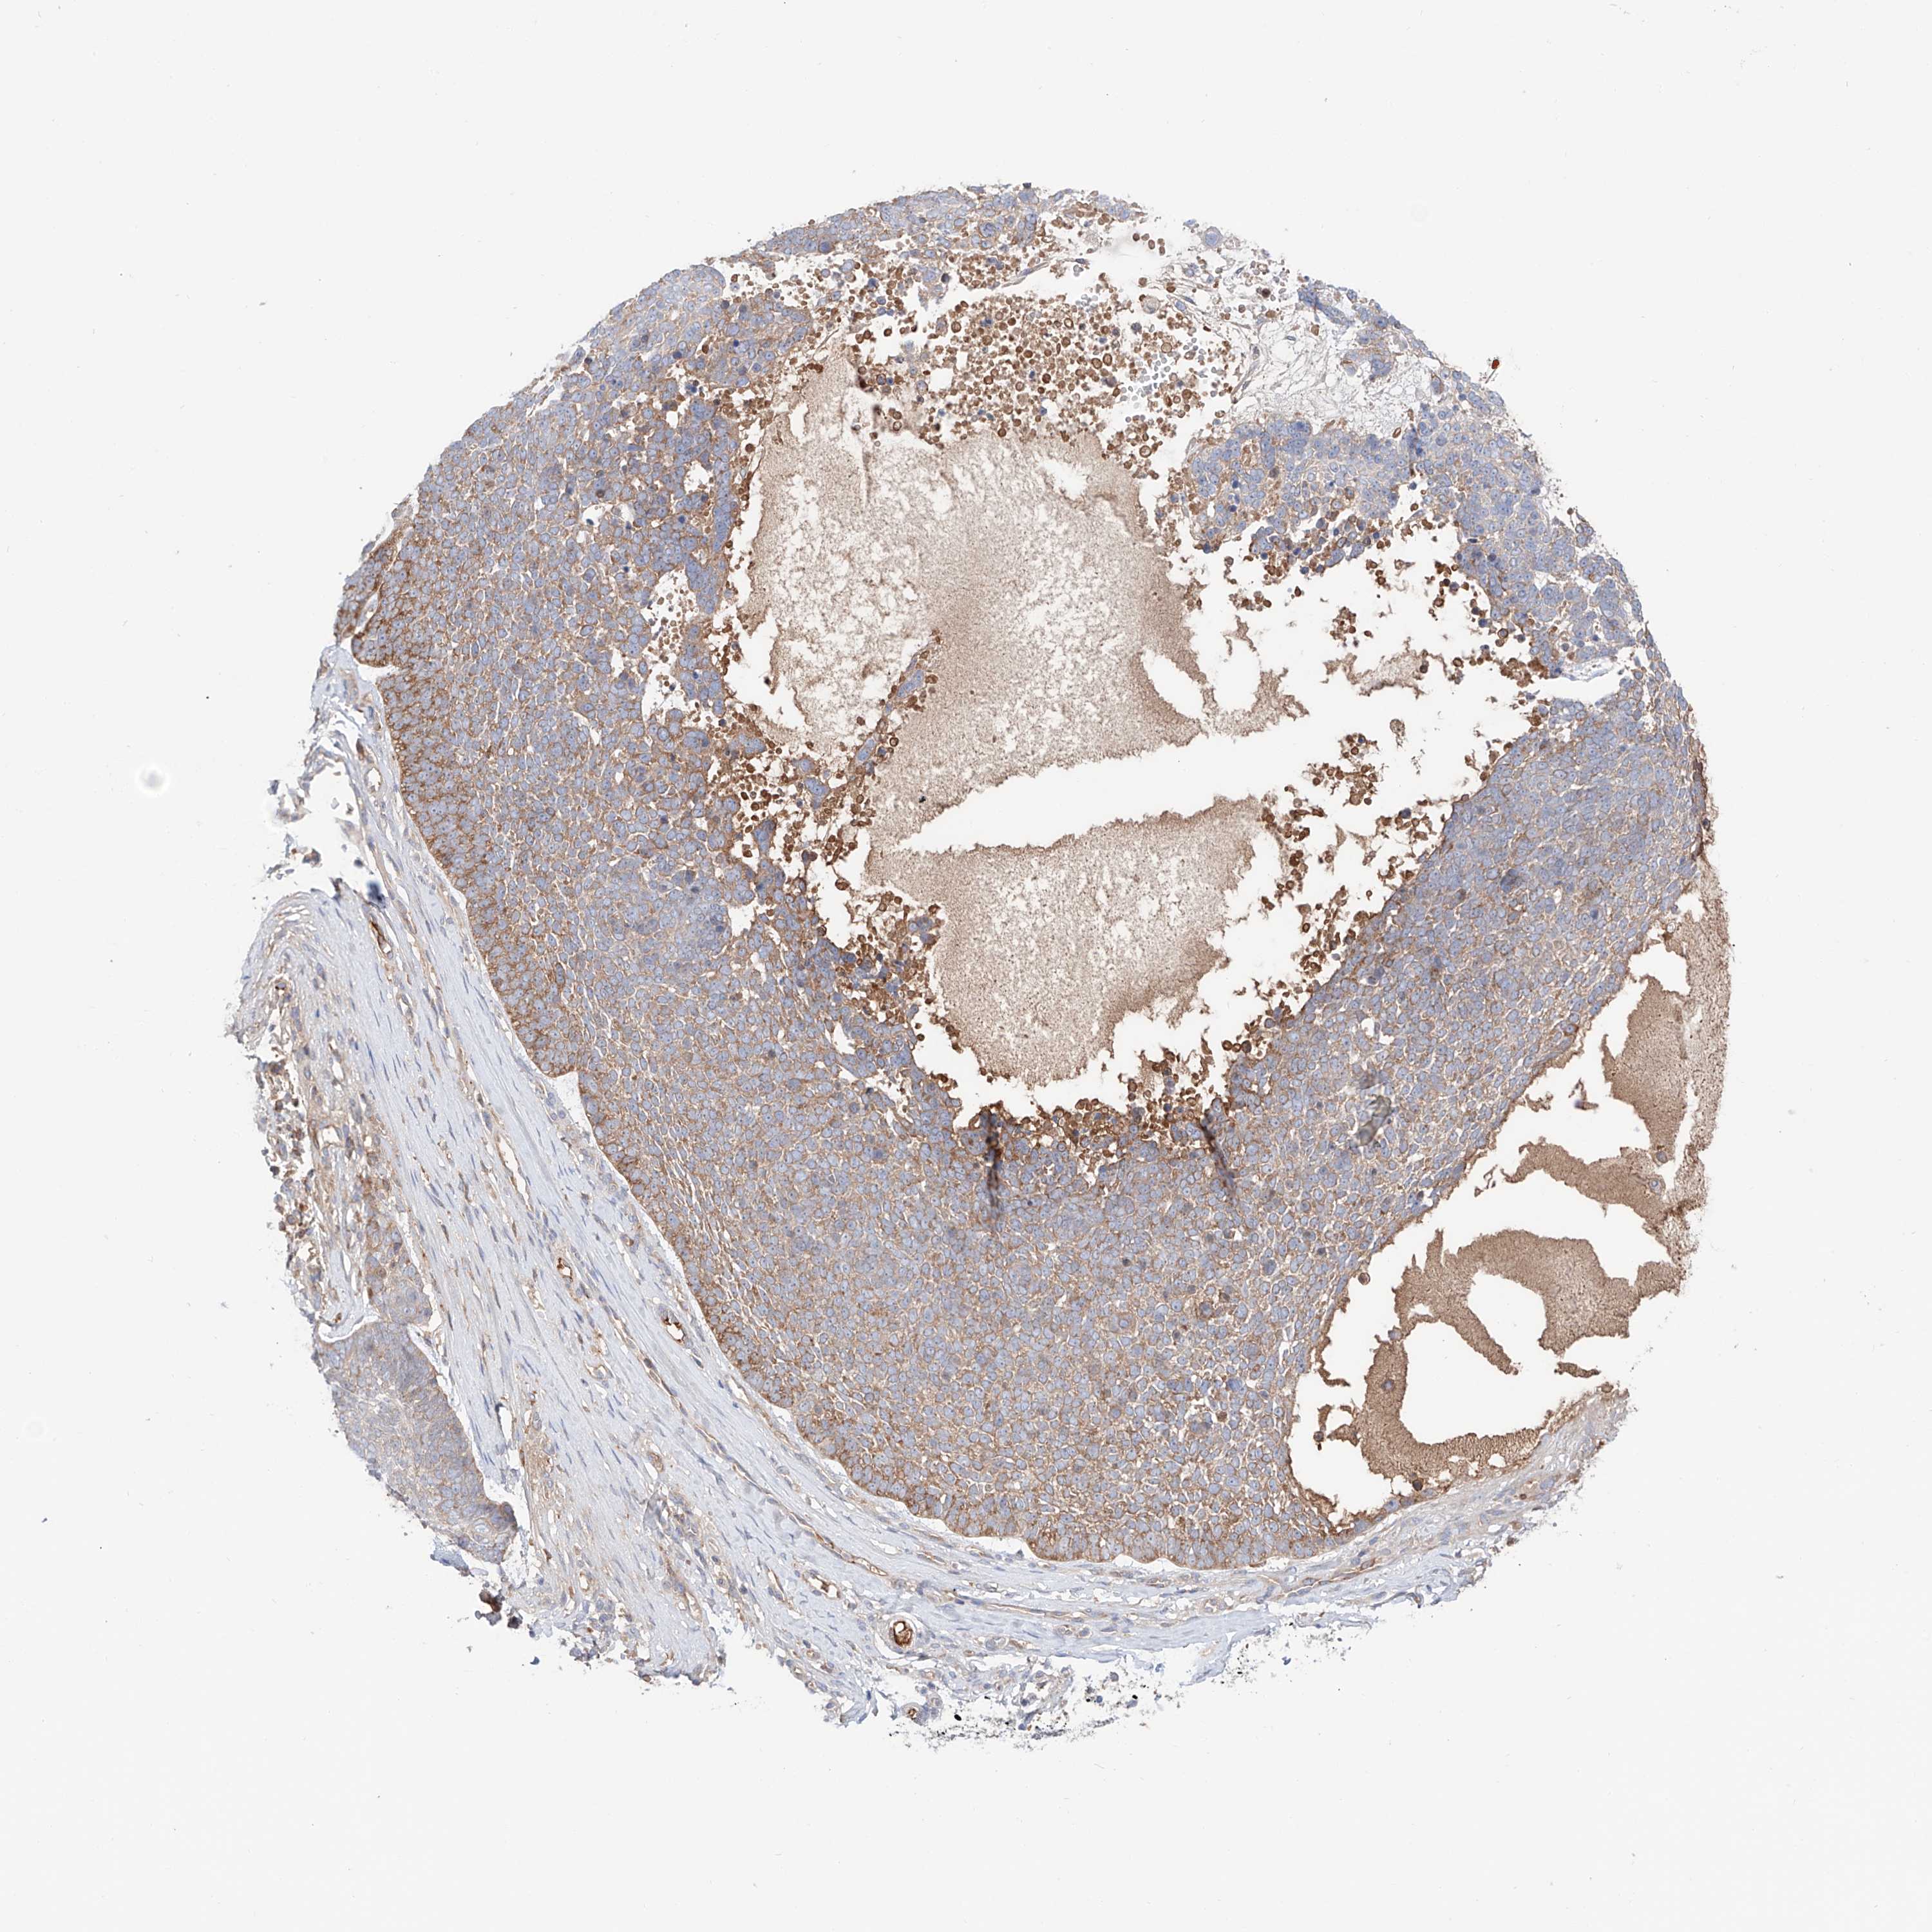

SKIN CANCER - Protein expressioni

A mouse-over function shows sample information and annotation data. Click on an image to view it in a full screen mode. Samples can be filtered based on level of antibody staining by selecting one or several of the following categories: high, medium, low and not detected. The assay and annotation is described here.

Antibody stainingi

Antibody staining in the annotated cell types in the current human tissue is reported as not detected, low, medium, or high, based on conventional immunohistochemistry profiling in selected tissues. This score is based on the combination of the staining intensity and fraction of stained cells.

Each image is clickable and will lead to virtual microscopy that enables deeper exploration of all samples and also displays staining intensity scores, fraction scores and subcellular localization as well as patient and tissue information for each sample.

Antibody HPA030646

Squamous cell carcinoma, NOS